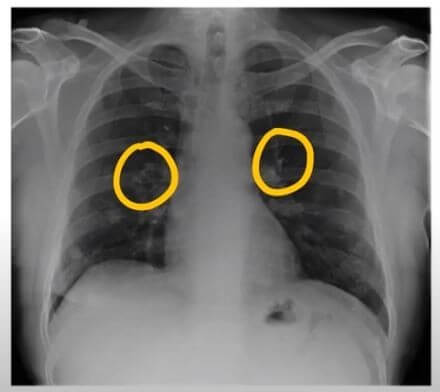

기흉의 정의

기흉은 폐의 표면과 흉벽 사이에 공기가 축적되는 상태를 말합니다. 이로 인해 폐가 충분히 팽창하지 못해 호흡 곤란과 통증을 유발합니다. 기흉은 자발적으로 발생할 수 있으며, 외상에 의해서도 발생할 수 있습니다.

기흉의 증상 기흉 증상은 흉통과 호흡곤란이 대표적입니다.

흉통은 대체로 갑자기 시작되며 24시간 정도가 지나면 사라집니다. 사람마다 흉통을 다르게 느낄 수 있는데, 등 쪽에서 담이 결린다고 하거나 숨쉴 때 가슴 통증이 느껴진다고 합니다.

호흡곤란은 환자의 상태에 따라 다르게 나타나며, 기존에 폐질환이 없는 사람의 경우 대체로 호흡곤란이 심하지는 않습니다. 하지만 기흉 증상이 심한 환자는 호흡이 불편할 정도의 호흡곤란을 느끼며 청색증이 동반될 수 있습니다.